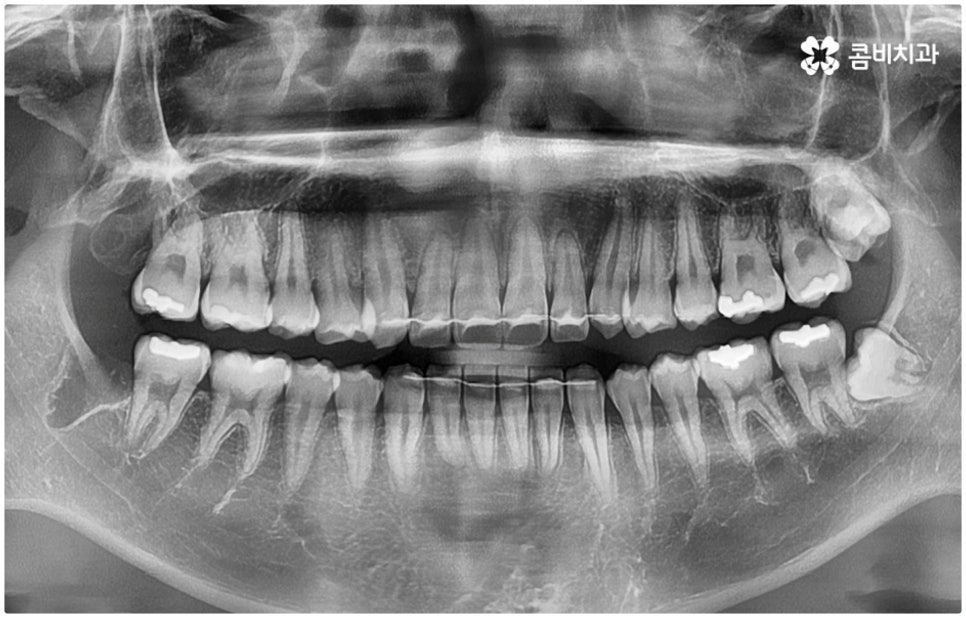

매복사랑니발치치과 를 선택할 때 어떤 것을 기준으로 고르는 것이 좋을까요? 사랑니가 완전히 매복되어 있다면 잇몸을 절개하고 상황에 따라 골삭제 후 치아를 조각내어 빼내줄 필요가 있는데 이러한 과정이 굉장히 까다롭기 때문에 먼저 환자분들의 사랑니 위치 및 뿌리의 형태, 인접 치아 구조, 주변 조직이나 신경 위치 등을 구체적으로 확인할 수 있는 3D CT와 같은 정밀 검진 장비를 갖추고 있는 매복사랑니발치치과 인지 체크해 보실 필요가 있어요.

하악 사랑니의 경우 하치조 신경을 건드리지 않도록 주의해야 하고 상악 사랑니의 경우 상악동 천공을 조심해야 하는데 이 때 환자분들의 상황 또한 개인마다 천차만별인 만큼 각각을 꼼꼼하게 살펴보고 섬세하게 발치 처치를 하기 위해 술자의 뛰어난 기술력 및 숙련도가 요구되므로 매복사랑니발치치과 의료진의 경력 사항을 면밀하게 살펴보시는 것도 도움이 될 거예요.

고난도 시술일수록 환자분들의 안전을 위해서 철저한 준비 과정이 필요하겠죠? 특히 술자가 관련 임상 경험이 풍부하고 다양한 케이스를 접해 본 노하우를 가지고 있어야 혹시 모를 신경 손상의 위험성이나 부작용, 상악동 천공시 생길 수 있는 감염 및 출혈과 같은 합병증 등에 대해서 충분히 인지하고 정확한 분석을 통해 사전 대비를 잘 할 수 있어요. 또한 정밀 검진 후 위치나 상황에 따라 무조건적인 발치를 하는 것이 아니라 지속적으로 관찰을 하거나 경과를 보면서 적절한 시기를 조율해 보는 것이 더 나을 수 있다는 판단을 내릴 수도 있는데 이런 경우에도 숙련된 의료진에게 자세한 설명을 듣고 상담을 충분히 하신다면 환자분들의 입장에서 보다 편안한 마음을 가지고 진료를 받으실 수 있을 거예요.